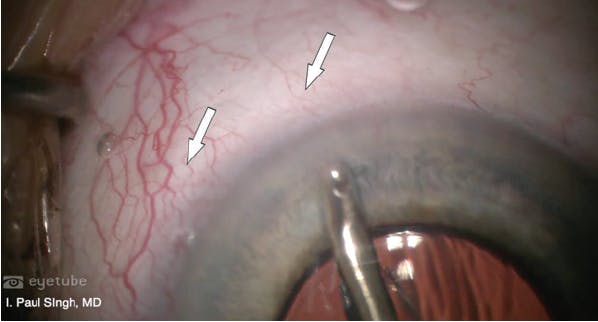

A 78-year-old patient presented with BCVA of 20/60 OD and 20/40 OS. The patient had ocular surface disease and a significant cataract in the right eye. Maximum IOP was 39 mm Hg OD and 33 mm Hg OS. IOP on four medications was 32 mm Hg OD and 22 mm Hg OS. Gonioscopy revealed an open angle and +2 pigmentation of the TM. The patient had a history of a failed Ex-Press shunt (Alcon) OD, rendering the conjunctiva unhealthy, as well as a history of failed SLT in both eyes, indicating likely resistance behind the TM, either in the Schlemm canal or distal channels. Corneal hysteresis was low, at around 7 OD and 8 OS (compared with a normal value of 10). This indicated that the shock-absorbing ability of the patient’s cornea might be poor, placing him at greater risk of glaucomatous progression.

Pachymetry was fairly normal, with a central corneal thickness of 523 μm OD and 534 μm OS. On OCT, however, the patient’s ganglion cell layer was almost negligible, the ganglion cell complex was wiped out, and the retinal nerve fiber layer in both eyes was extremely thin (Figure 9). The right eye showed a notch in the inferior rim. VF testing revealed paracentral loss with a superior defect in the right eye that was consistent with the retinal nerve fiber layer loss and disc notch. Moderate disease was also indicated in the left eye by VF testing.

Figure 9. The patient’s ganglion cell layer was almost negligible, the ganglion cell complex was wiped out, and the retinal nerve fiber layer in both eyes was extremely thin.

Given this diagnostic picture and the patient’s concerns about coming into the office, I decided to utilize a combined approach including 360° viscodilation with the Omni Surgical System (Sight Sciences), 180° goniotomy, implantation of a Hydrus Microstent (Ivantis), and cataract extraction (Video 5). With the Omni device, I engaged the TM at about a 45° angle and advanced the nylon thread 180° in one direction. As the thread was retracted, OVD was released to dilate the canal and distal channels. I then performed the same technique to address the other 180°, but after viscodilation, I rethreaded the canal and then performed a 180° goniotomy. Next, addressing the part of the angle that was not cut, I placed a Hydrus stent, which not only bypasses the TM but also scaffolds Schlemm canal. Performing viscodilation first enables the Hydrus to slip in beautifully.

In this case, I was able to maximize distal outflow via viscodilation, cut the TM about 180°, and, in the other 180°, place a scaffolding device to maximize outflow through the conventional pathway. On postoperative day 1, IOP was 18 mm Hg. At postoperative month 1, IOP was 14 mm Hg and UCVA was 20/30 on brimonidine-timolol only. For this 78-year-old patient with IOP in the 30s mm Hg on four medications, by mixing MIGS I was able to maximize efficacy, decrease IOP and the number of glaucoma medications, and minimize the number of postoperative visits required compared with traditional glaucoma surgery.